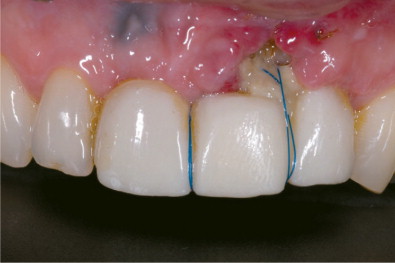

Một trường hợp ghép nướu không thành công hoàn toàn do bị lộ mảnh ghép

Mất mô ghép: Nếu mô ghép không được cấp máu đủ hoặc không kết hợp tốt với mô tại vị trí ghép, có nguy cơ mô ghép bị tiêu đi hoặc không lành hẳn. Điều này có thể gây tái phát tụt nướu. Nếu BS tay nghề không cao và không đủ kinh nghiệm, hoặc trong một số trường hợp quá phức tạp hay chẩn đoạn sai nguyên nhân, tình trạng tụt nướu có thể diễn ra nghiêm trọng hơn, Khi đó, việc ghép lại là cần thiết